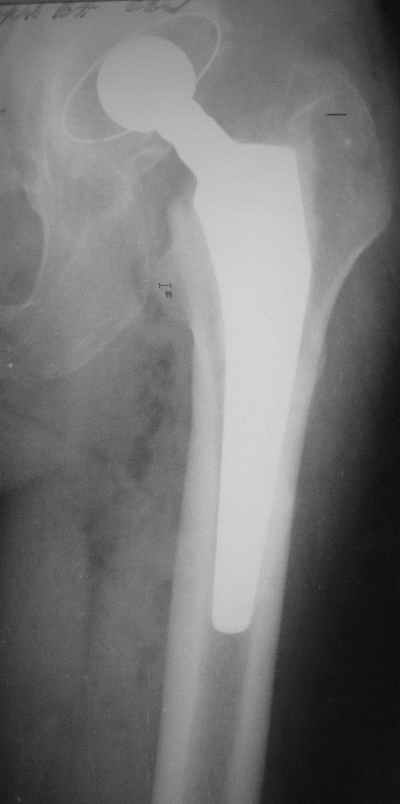

Уважаемые коллеги, Мужчина, 69 лет, в декабре 2004 г перенес тотальную цементную артропластику

Через 3 мес после операции на фоне прогрессирующих болей в средней и проксимальной третях бедра при нагрузке возникли резкие боли и появилось опухолевидное болезненно образование. Процесс сопровождался резким одномоментным укорочением ноги.

В феврале 2005 г. выполнена ревизионная артропластика, завершившаяся прогрессировавшим в течение 1-2 мес укорочением ноги. В настоящее время ходит только с костылями, при движениях в тазобедренном суставе испытывает резкие боли, ощущает хруст. Попытка осевой нагрузки бедра сопровождается ощущением "перемещения поршня" и заметным по внешним ориентирам укорочением левой ноги на 1-1,5 см.